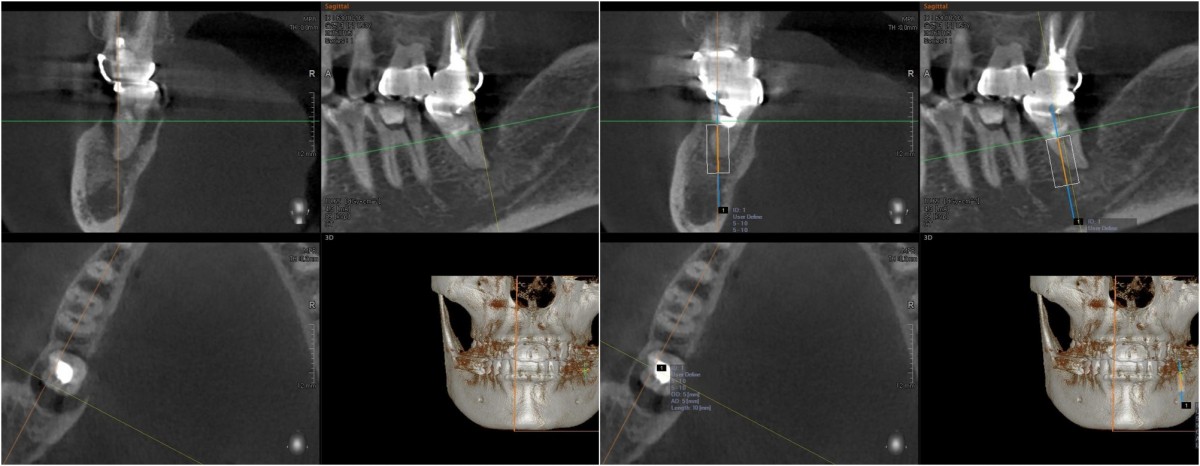

▲CBCT view. 8 years after occlusal loading.